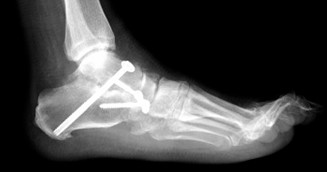

В ходе процедуры удаляются хрящевые поверхности суставов, и кости фиксируются в анатомически выгодном положении металлическими конструкциями, такими как винты или пластины.